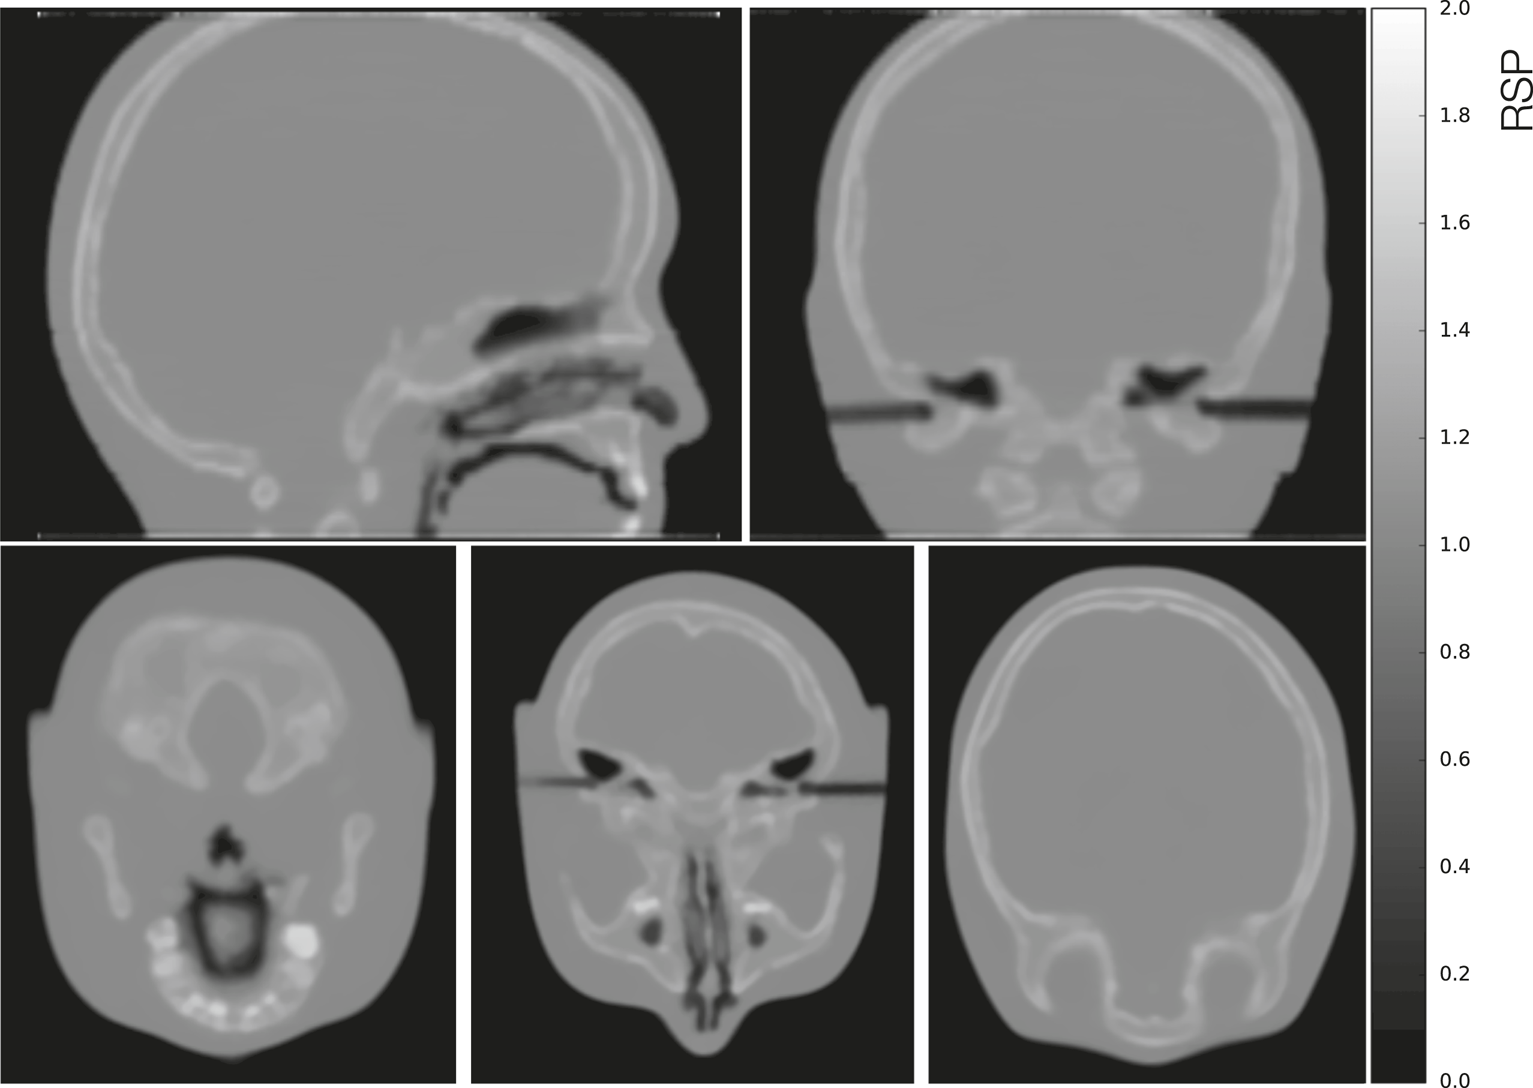

The CTP404 phantom reconstructed with a simulated full pCT scan is shown in Figure 13A using the DTC modeled setup. In Figure 13B a comparison of the average RSP percent errors (calculated as the difference between the reconstructed value and the reference value, divided by the reference value) for each material in the CTP404 phantom (excluding air) for the ideal and the modeled setups is shown. The mean RSP values were measured in a small area (shown in Figure 13A by the small colored circles) in the center of each insert and averaged over 10 reconstructed slices. The error bars represent the relative standard deviation of each RSP distribution. For both the setups the RSP error for each material is below 0.5%. Although in most cases (except for PMMA and Delrin) the RSP error is smaller for the modeled setup than the ideal, the error bars for the modeled setup are sometimes two times as big as the errors, indicating a high level of noise for the modeled setup. The average error for all the materials in the CTP404 phantom is 0.214 and 0.162% for the ideal and the modeled setups, respectively. In Figure 14 different views of the head phantom reconstructed for the modeled setup are shown. The images result clean with no artifacts and all the salient structures in the head (brain, bones, teeth, and air cavities) are well distinguishable. The reconstruction time for these images was 4,383.17 s (about 1.5 h) using an Intel® Xeon® E5-2697 v2 CPU @ 2.70GHz with 48 cores, and an NVIDIA® GeForce GTX 650 GPU.

FIGURE 14

From top left to bottom left clockwise: Sagittal, coronal, and three axial views of a full pCT reconstruction of the simulated head phantom in the modeled setup.